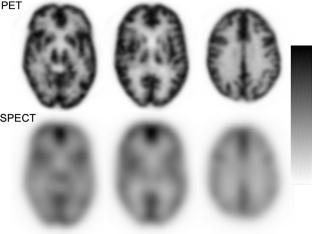

A 3D-PET/CT scanner, Discovery IQ, which has a 5-ring configuration with a 26 cm axial field of view, was used. A 100 mL saline pack containing 11C at 460 MBq was placed on a 3D Hoffman brain phantom (HBP) filled with 18F at 5.0 kBq/mL, and dynamic scans were performed. The quantitative capability of measured radioactivity in the HBP was evaluated. Subsequently, the HBP filled with 18F at 5.0 kBq/mL was equipped with a gas mask system, and 15O-gas was administered at flow rates ranging from 3000 MBq/min, decreasing in 500 MBq/min increments, while dynamic scans were performed. The quantitative accuracy of radioactivity in HBP and count rate characteristics were evaluated. To confirm the feasibility of the 15O-gas PET method in the clinical situations both practically and quantitatively, cerebral blood-flow (CBF) values obtained via PET and SPECT were compared in 10 patients with cerebrovascular diseases. CBF was calculated by the autoradiography method. Analyses included standard brain transformation and alignment, followed by averaging CBF values from 26 brain regions for comparison.

The measured radioactivity in the HBP approached the true value as the radioactivity of 11C in the saline pack decreased. To achieve a quantitative error within ± 5%, the radioactivity of 11C needed to be below 40 MBq. Similarly, for 15O-gas PET, an administration rate below 1000 MBq/min was needed to maintain quantitative accuracy within ± 5%. When exceeding 1500 MBq/min, random events surpassed 50%, compromising reliability. The correlation coefficient between PET and SPECT-derived CBF was 0.39 (p < 0.001). After excluding two outliers, it improved to 0.71 (p < 0.001), indicating a strong correlation. PET-measured CBF tended to be higher than SPECT.